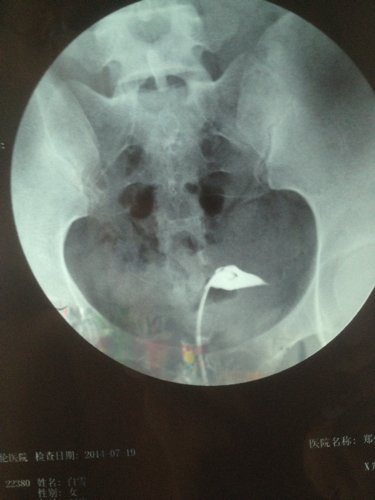

帮我看看这个X光照影,输卵管通不通?粘连吗? 点击展开 匿名用户 2014-07-22 10:32 为您推荐: 其他回答 你好,这个不一定的,平时的时候亲最好让大夫详细的检查一下比较放心的哦,平时多注意休息 斑驳的流年88 2014-07-22 10:35 相关问题 郑州怎么查输卵管通不通?输卵管不通粘连 我吃了活血化瘀的中药左侧附件隐隐作痛是什么原因呢(曾宫外孕切除了右侧输卵管)(现在左侧伞端粘连不通 子宫右倾,宫劲宫腔重度粘连,右侧输卵管不通??